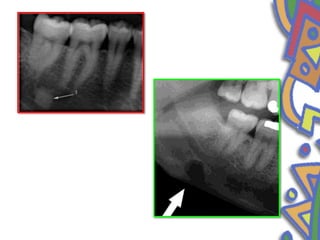

• Periapical idiopathic osteosclerosis

• Enostosis

• Dense bone island

• Localized growth of compact bone

• Asymptomatic

• vary in size from 2 mm to 1-2 cm.

• Mandible

• Premolar molar area

• Radiographic image- radiopaque

• Etiology – no

• margins or capsule

• D/D

• Stafne bone defect

• First described by Stafne in 1942

• The exact pathogenesis is still obscure.

• Epidemiology

• Men in their

• fifth or seventh decade of life

• Stafne suggested that the cavity could result from a failure of

normal bone deposition in the region formerly occupied by

cartilage .

• localized pressure atrophy of the lingual surface of the

mandible from the adjacent salivary gland

• Clinical features

• Present as asymptomatic radiolucency below the mandibular canal in

the posterior mandible between the molar and angle of mandible

• well circumscribed

• sclerotic border

• Superimposed over the apices of anterior teeth

• Stable in size

• 1 to 3cm in diameter

• below the inferior dental canal

• Incidental